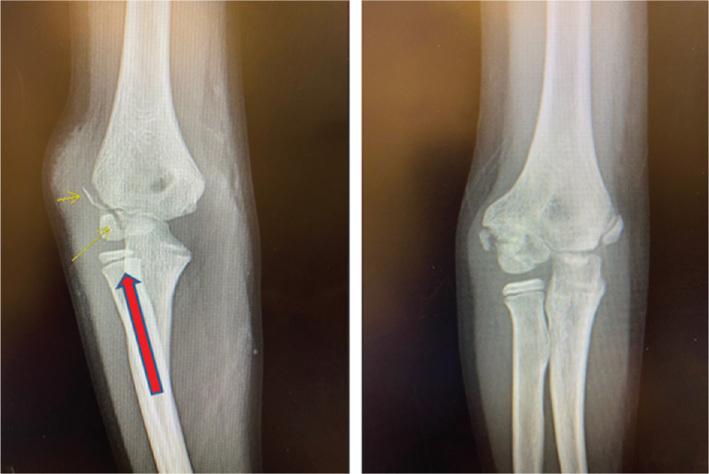

Lateral condyle fractures are the second most common elbow fracture in pediatric patients. Unlike supracondylar humerus fractures, these injuries involve the articular surface and present unique challenges. These injuries are graded based on the degree of displacement and this dictates your treatment. Both closed and open techniques are appropriate depending on the degree of displacement. Our preferred technique for open reduction and internal fixation is described and illustrated in the accompanying video. •Lateral condyle fractures are common elbow injuries in the pediatric population affecting the articular surface.•Accurate reduction of articular surface is critical.•In order to promote healing, these fractures often require longer immobilization than supracondylar fractures due to intraarticular nature of the injury.•Blood supply to the capitellum enters posteriorly, so one must be cautious with posterior dissection.

外侧髁骨折是儿科患者中第二常见的肘部骨折。与肱骨髁上骨折不同,这些损伤累及关节面并带来独特的挑战。这些损伤根据移位程度分级,这决定了治疗方式。根据移位程度,闭合和开放技术都适用。随附视频中描述并展示了我们首选的切开复位内固定技术。